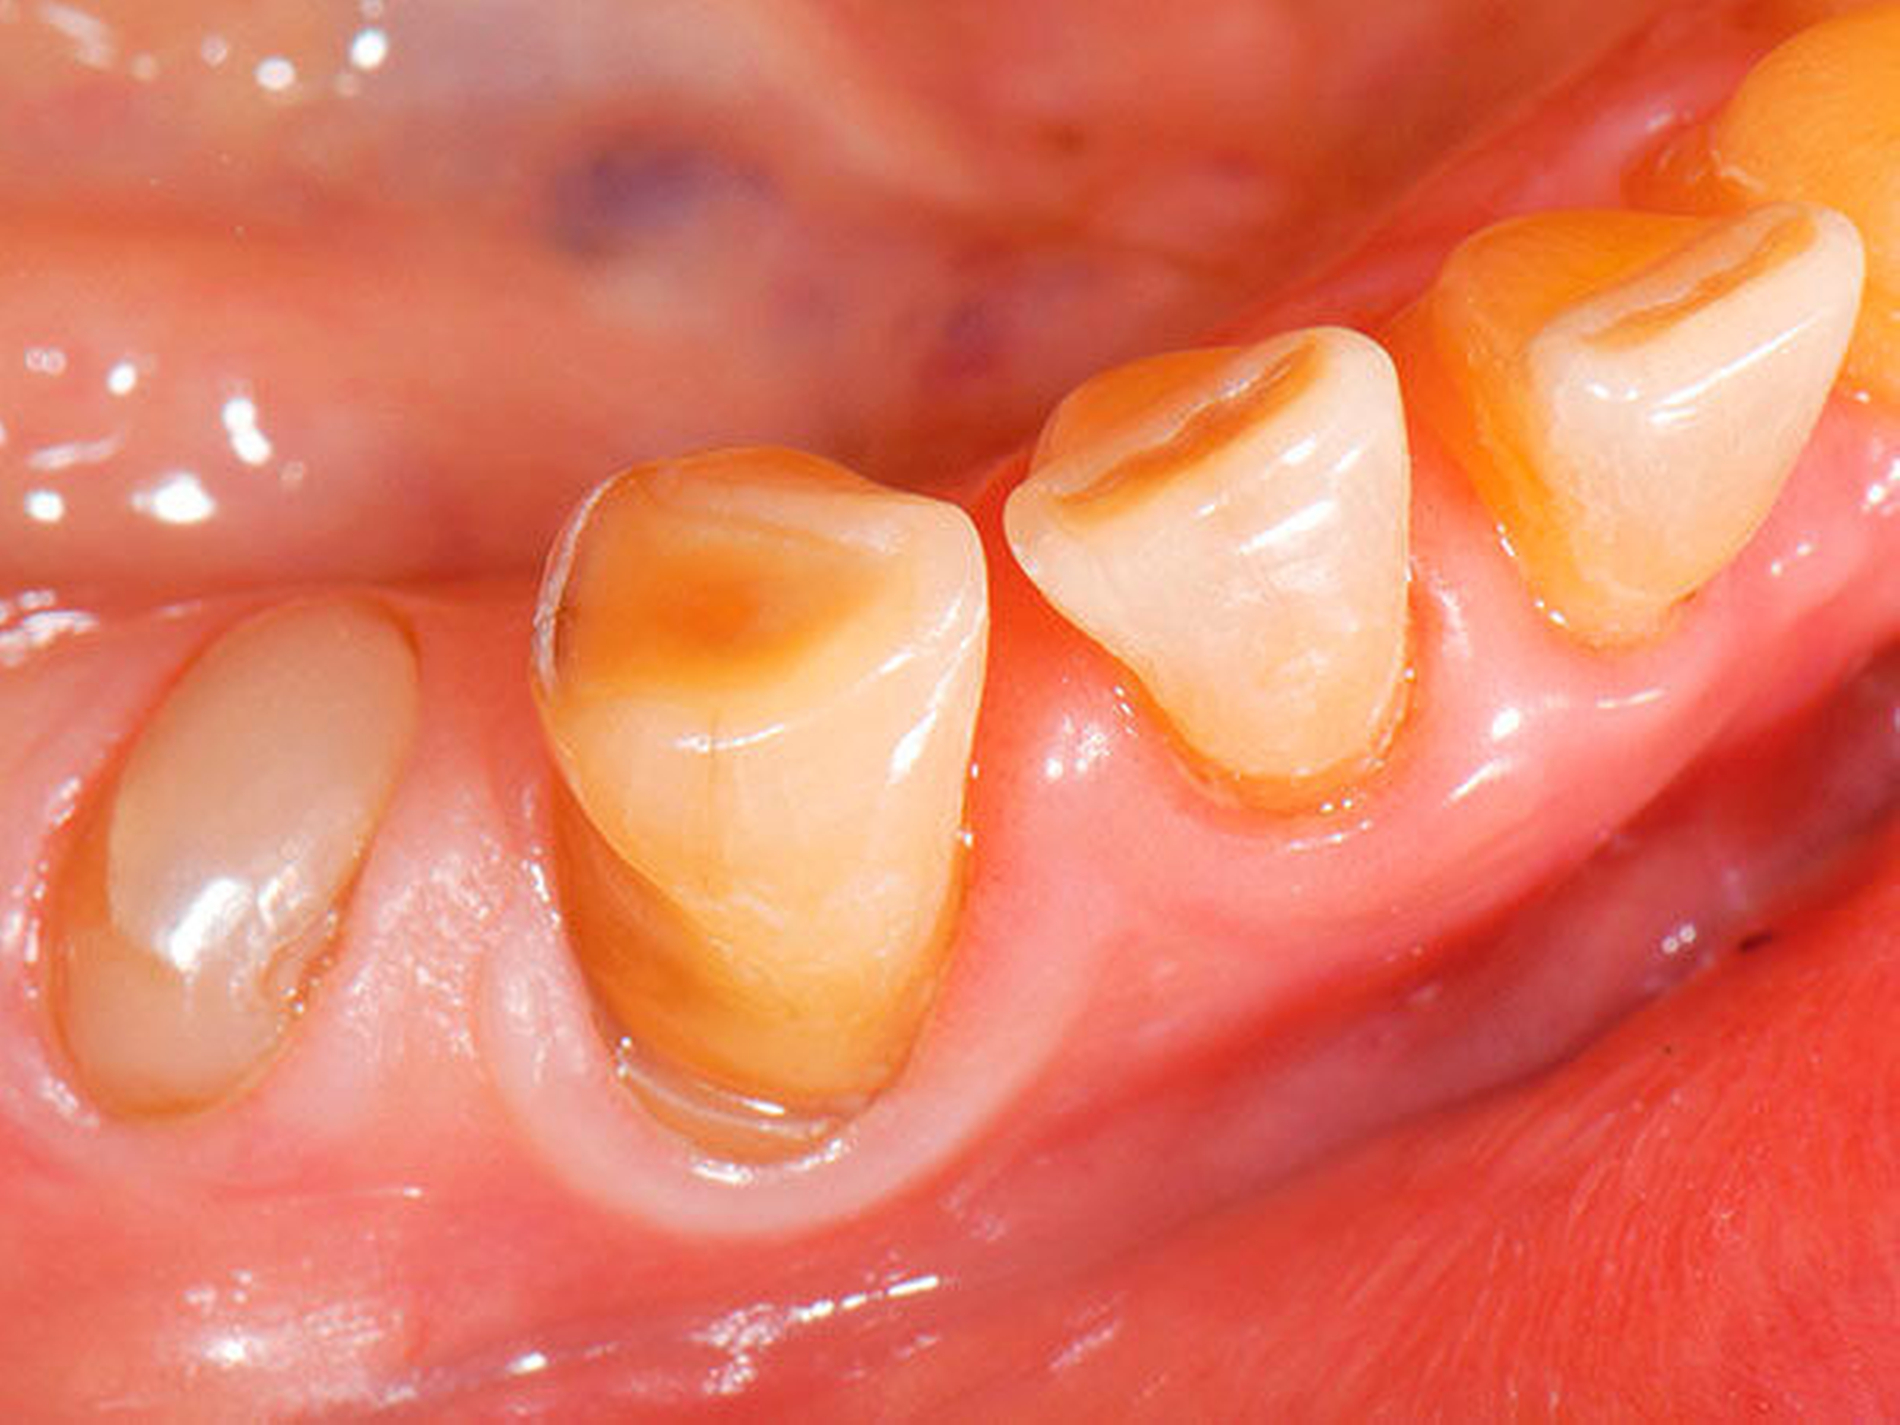

3. Restaurative Versorgungen bei Wurzelkaries

Freiliegende Wurzeloberflächen können im Alter ein locus minoris resistentiae für Karies sein. Im Zusammenspiel ungünstiger Ernährungsgewohnheiten, nachlassender Mundhygiene sowie Änderungen von Speichelquantität und -qualität kommt es zuweilen zu einem präventiv und restaurativ schwer beherrschbaren Auftreten von Wurzelkaries. Gut zugängliche Kariesläsionen können mit einphasig eingebrachtem Komposit (R1-Restaurationen) angegangen werden (Abbildungen 3 bis 5). Bei schwerer zugänglichen Arealen kommt ein zweiphasiges Vorgehen in Betracht (R2-Restaurationen). Das Vorgehen bei der R1- und bei der R2-Technik wurde mehrfach beschrieben [Frese et al., 2014a, b, c, d; Staehle et al., 2014, 2017]. Im Fall von zirkulärer Wurzelkaries sollte frühzeitig eingegriffen werden, da ansonsten die gesamte Zahnkrone frakturieren kann.

Abbildung 3: ausgedehnte Kronen- und Wurzelkaries unter einer Krone am Pfeilerzahn 47 einer seit Jahrzehnten eingegliederten Brücke von 45–47 bei einer 71-jährigen Patientin, die nach einer zerebrovaskulären Erkrankung unter Antikoagulantientherapie steht, vor etwa zwei Jahren hat sie eine Umstellung auf eine fluoridfreie Zahnpaste vorgenommen.